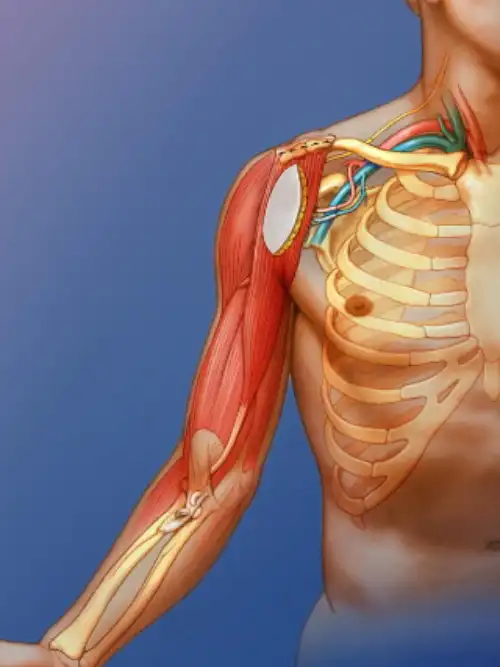

What is the brachial plexus?

The brachial plexus is a network of nerves in the neck and shoulder region (see the video above). It is made up from 5 large nerves which come out of the spinal cord between the vertebrae (bones in the neck), pass under the clavicle (collar bone) and into the upper arm. These nerves enable the signals that allow movement and feeling to reach the arm. These nerves are represented in speech and writing by these symbols: C5, C6, C7, C8, T1 (C=cervical, T=thoracic)

Nerves are cord-like structures made of numerous nerve fibers that transmit electrical signals between the brain, spinal cord, and body tissues. They enable movement and sensation by carrying messages from the brain to muscles and sensory information back to the brain. When nerve fibers are damaged, the connected muscles may weaken even if the muscle itself is unharmed. The nervous system functions by sensing changes, interpreting them, and triggering appropriate motor responses through sensory and motor neurons.